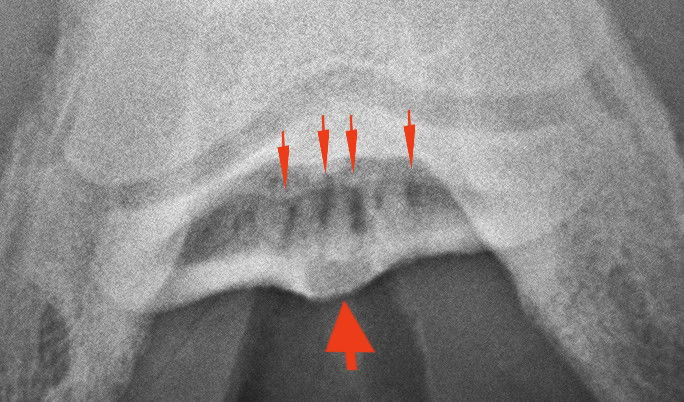

A nyírcsont vizsgálatára szolgáló un. oxspring felvétel. A nyilak a nyírcsontot mutatják.

Klasszikus „teniszütő” elváltozások.